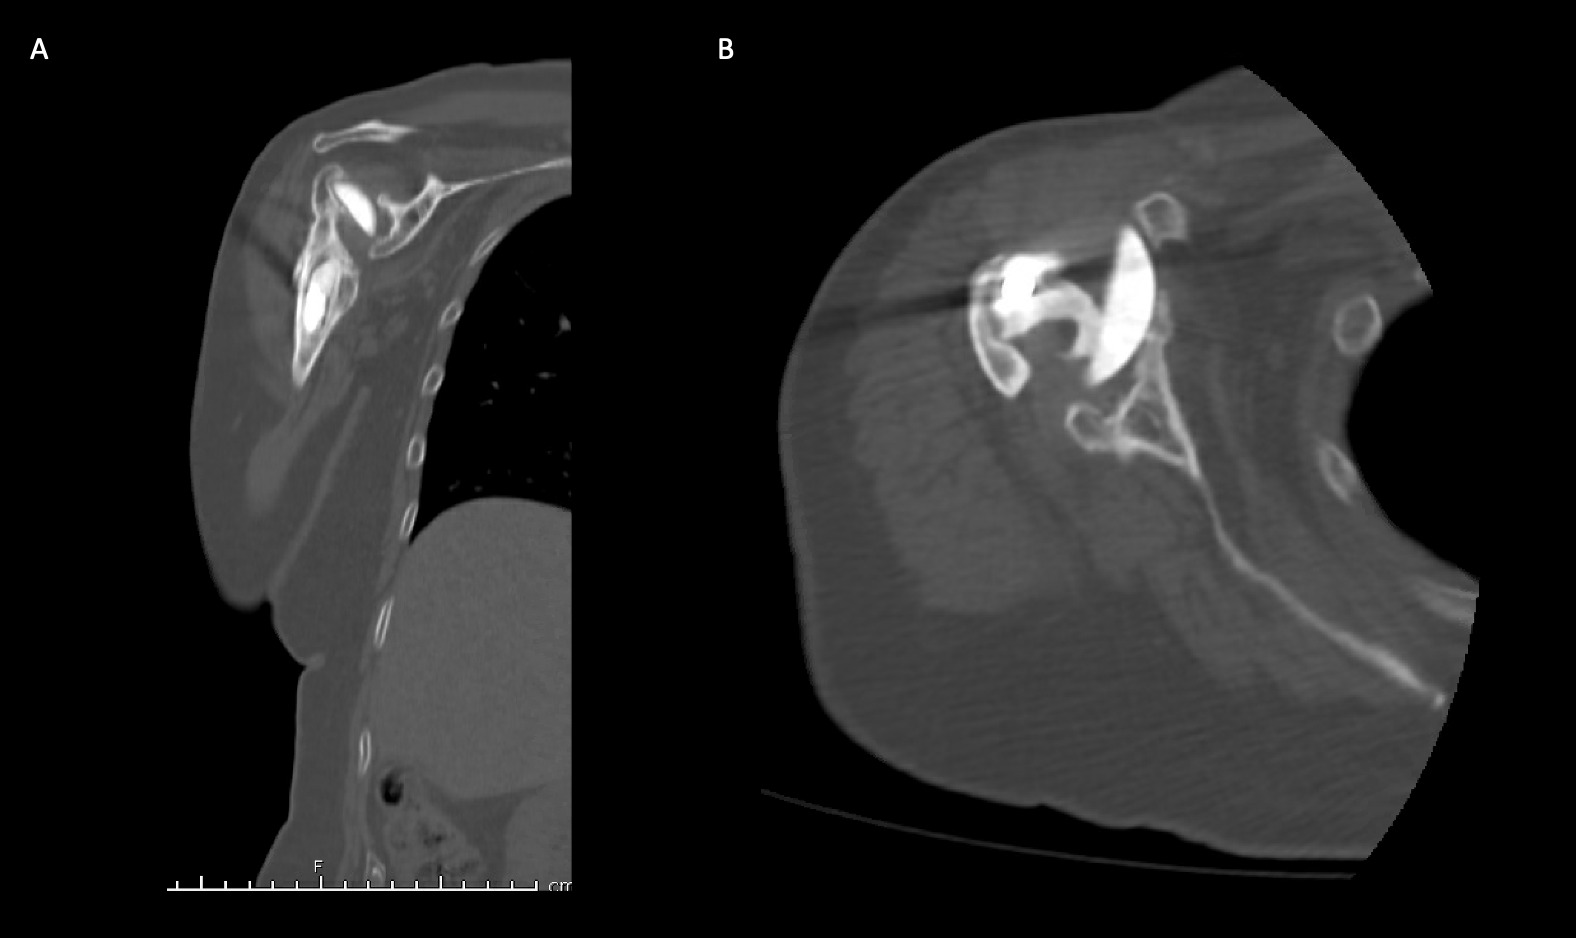

A 62-year-old woman presented for evaluation of her reconstructive options after resection arthroplasty of a right rTSA and completion of antibiotic treatment for culture negative PJI. Her rTSA had been an Encore prosthesis placed due to rotator cuff arthropathy (Figures 6). Post-operatively she had persistent pain, stiffness, and tenderness to palpation that was treated with physical therapy, a steroid injection, and manipulation under anesthesia. An infectious work up due to the chronic and persistent nature of the pain showed WBC 7.4, ESR 53, CRP 1.2. Patient denied further work up with a tagged white cell scan and preferred continued clinical monitoring to observe pattern of symptoms. Eleven months later, she endorsed persistent pain. Repeat infectious work up showed WBC 4.5, ESR 13, and CRP 1.1. Despite the normal inflammatory markers, a 10-day trial of Augmentin was initiated and failed to change her symptoms. The decision to proceed with 1 vs 2 stage reconstruction was made. During resection arthroplasty, a substantial amount of fluid was expressed from the joint capsule concerning for PJI. A cement spacer was placed, and the patient was treated with 6 weeks of vancomycin and cefepime (Figure 7). There was proximal humeral bone loss as the result of resection arthroplasty due to the humeral stem. The glenoid component was loose and associated with glenoid bone loss, further complicated by the need for removal of a broken central screw (Figure 8).

Intra-operative frozen sections, tissue cultures, and gram stain showed no signs of infection. Following treatment, inflammatory markers remained normal (WBC 5.5, ESR 22, CRP 0.9), and aspiration of the shoulder showed no organisms on gram stain and no growth on aerobic, anaerobic, fungal, and acid-fast bacilli cultures. Cultures were held for 21 days to rule out C. Acnes infection. She was left with profoundly limited active motion and severe pain and the patient elected to proceed with revision surgery. Because of the combination of severe glenoid and humeral bone loss and the lack of rotator cuff attachments necessitating a design with additional constraint, the decision to proceed with custom prosthesis design was made 9 weeks after resection arthroplasty.

Case 2. At the latest follow-up one-year post-op, the patient expressed that the pre-operative pain had resolved after the operation. Despite this, she stated that if given the option again she would not undergo the surgery because she did not attain the function she expected and felt that her function may have decreased compared to pre-op. Overall stability and alignment were good. On physical exam, she was able to reach within 1 inch from her mouth and had 20 degrees abduction and 5 degrees forward flexion actively. Active elbow flexion was 0 to 120 degrees (Figures 14). At 2 years post-op she had some regression in her pain but accompanied by modestly decreased AROM. Shoulder AROM was 15 degrees abduction, and 5 degrees forward flexion. Elbow AROM was from 0 to 105 degrees of elbow flexion. CT scan showed increased lucency surrounding the humeral component concerning for osteolysis and prosthesis loosening (Figure 14). Blood work at the 2-year mark to investigate the radiolucencies and decreased AROM left us with low suspicion for infection (WBC 5.4, ESR 33, CRP <3.0).